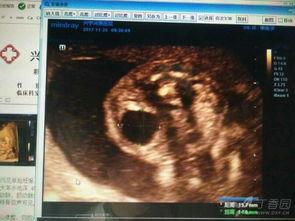

1. 视频中,医生通过超声波展示了宝宝在妈妈肚子里的样子,可以看到宝宝的头部、身体、四肢都十分清晰。

2. 视频还展示了宝宝的胎动,看着宝宝在妈妈肚子里翻滚、踢腿,是不是觉得既神奇又可爱呢?